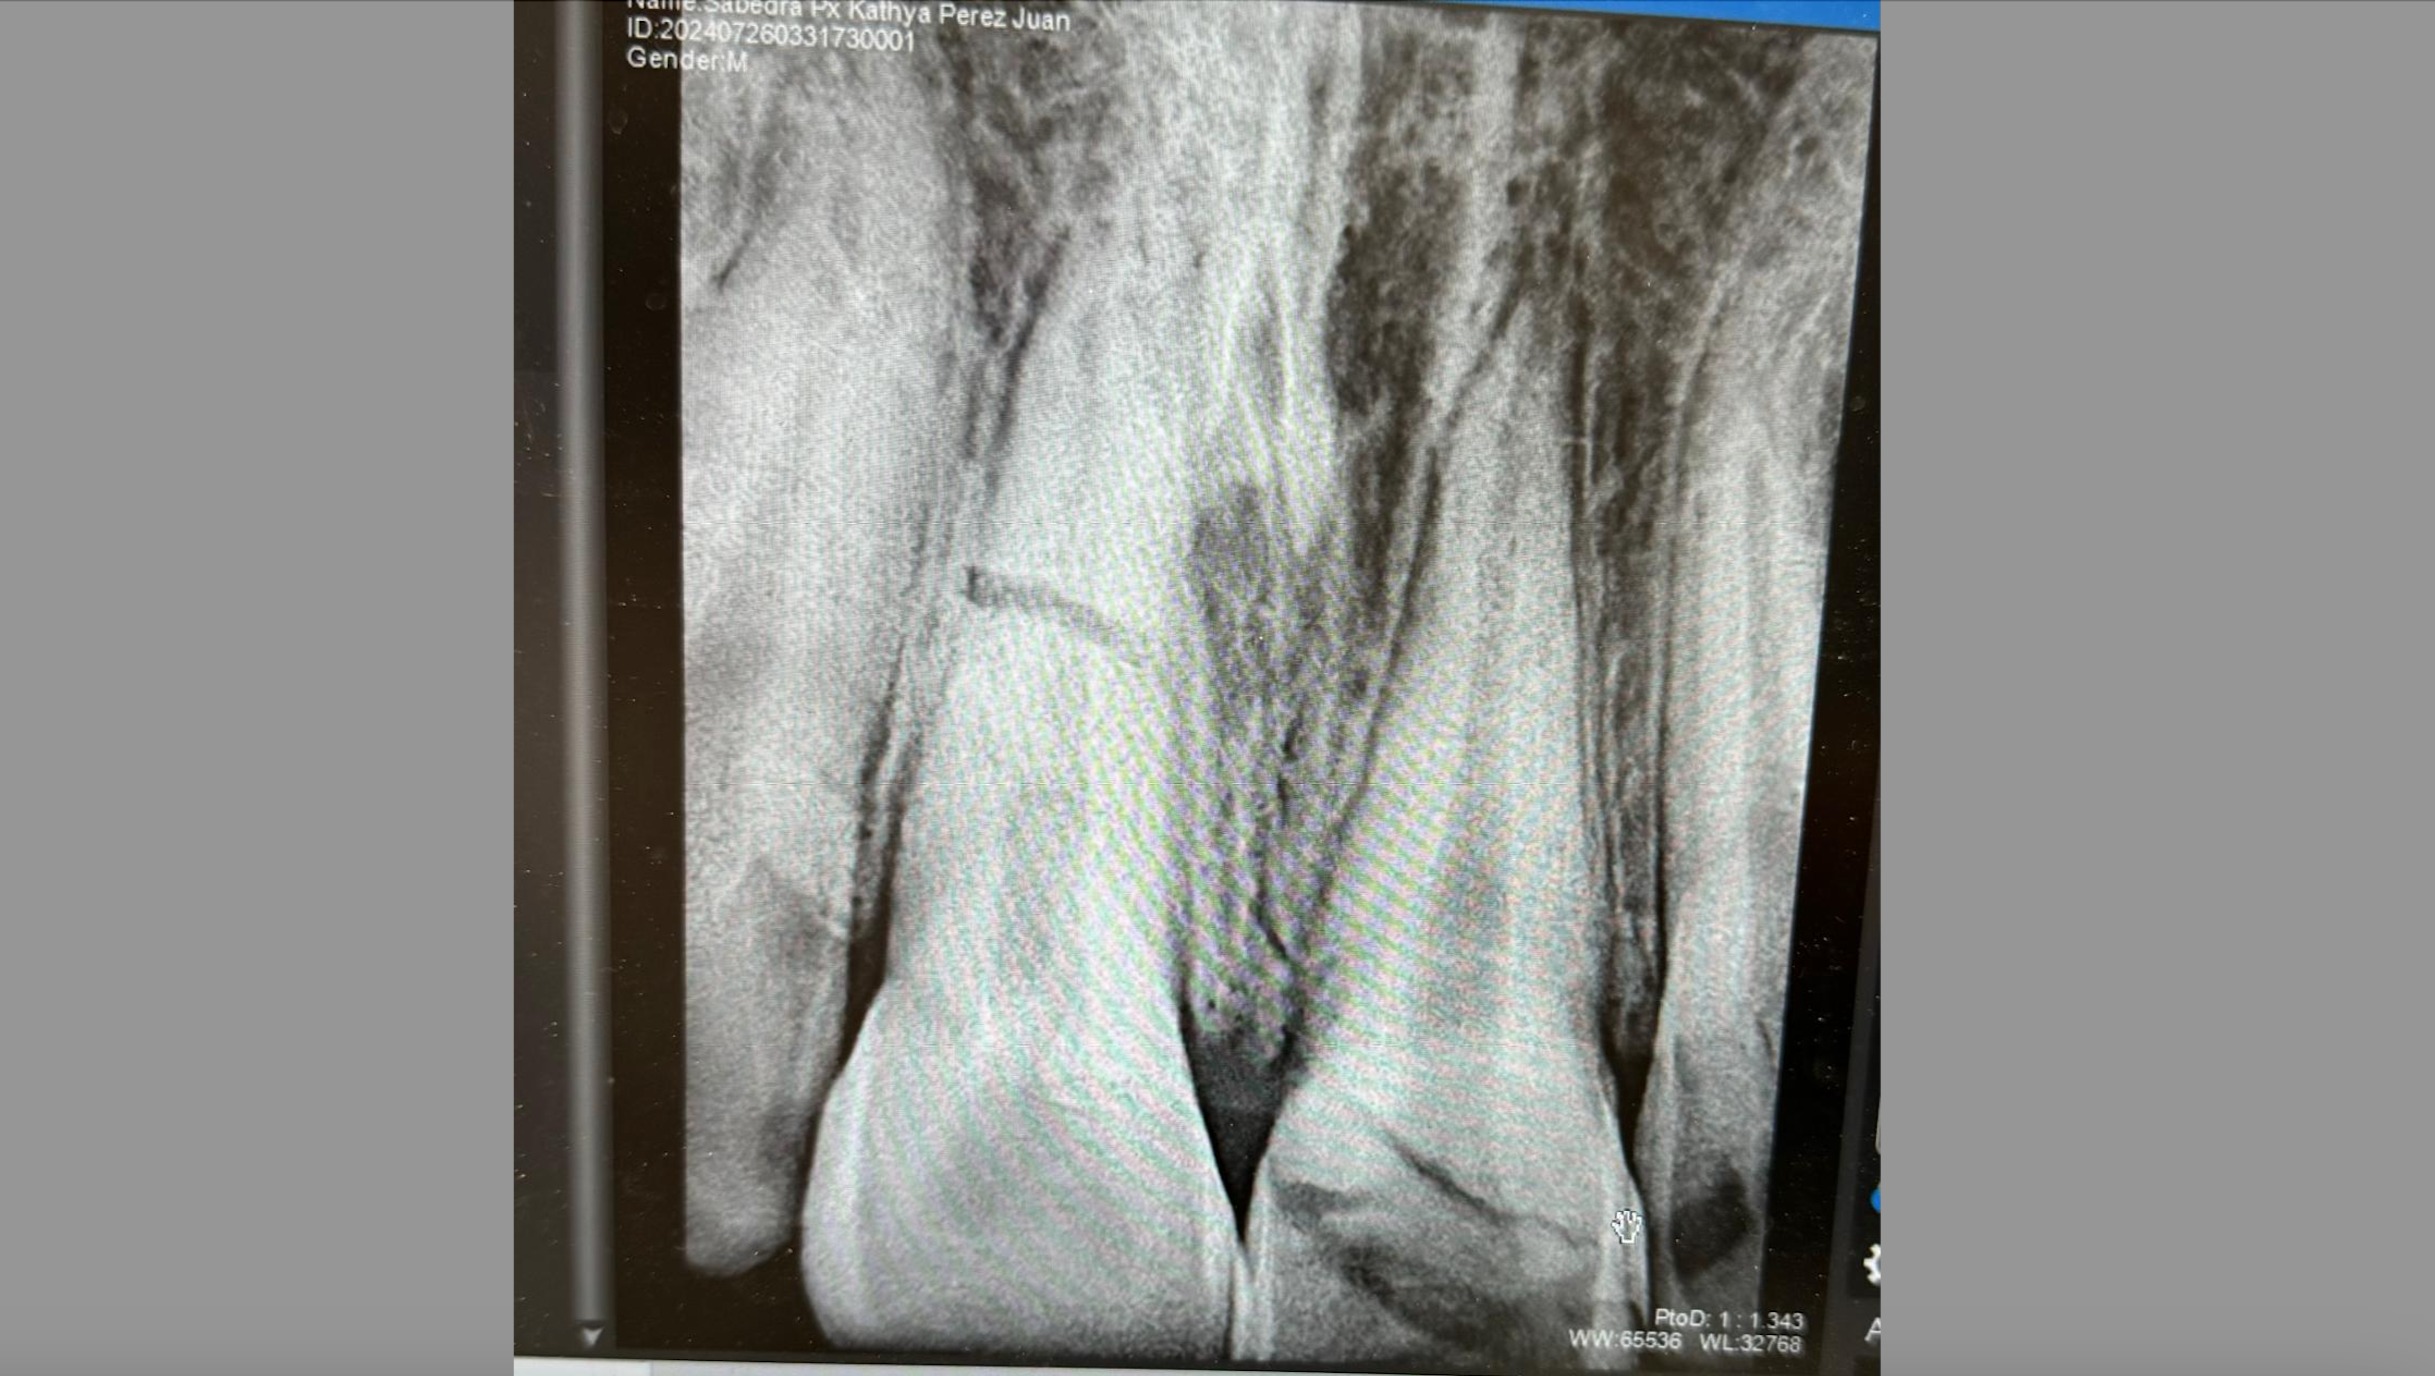

Él se golpeó los dos dientes frontales en un accidente, uno de ellos no se pudo rescatar, siendo necesario realizar endodocia y colocar una corona que usará mientras cumple la mayoría de edad, posteriormente se evaluara si necesita cambio, el otro diente se le fracturó de la raíz en este caso el diente estará en observación durante aproximadamente 6 meses para tratar salvarlo. Buscamos lograr apoyarlo para que pueda solventar los gastos de este tratamiento el cuál no es un proceso fácil, esperamos poder contar con su apoyo